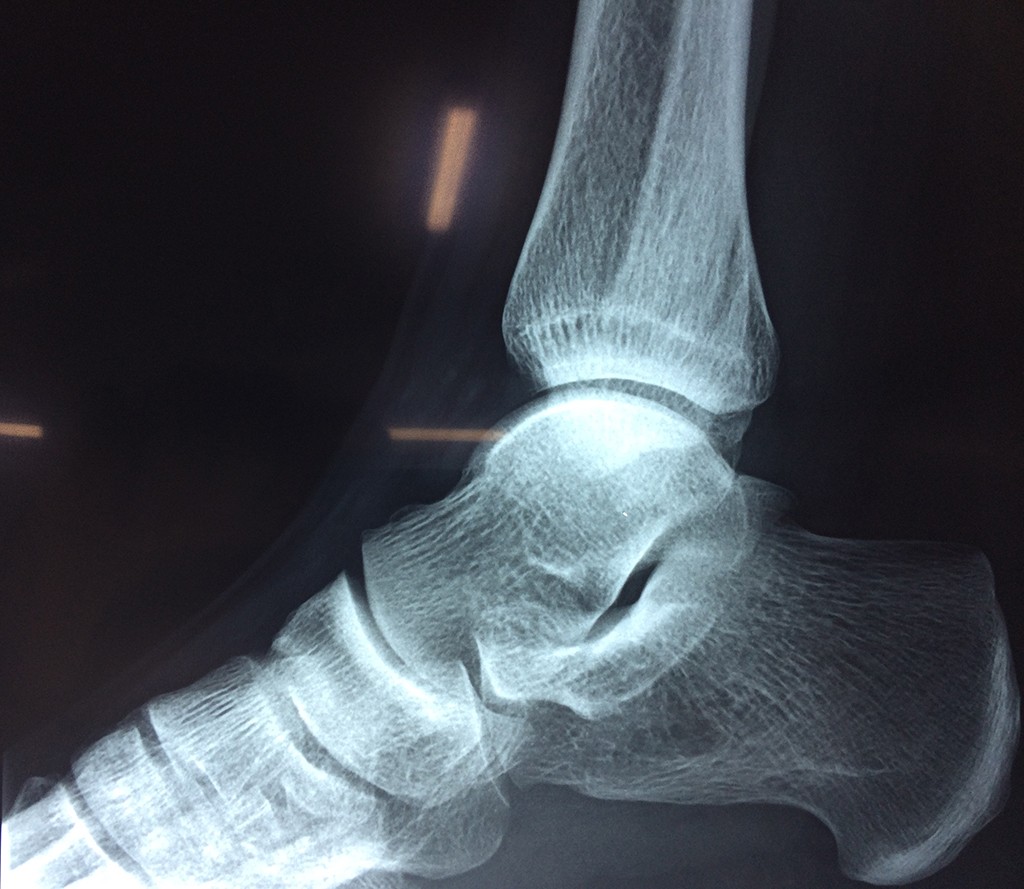

Una fractura de tobillo es la rotura de uno o más de los huesos del tobillo. Estas fracturas pueden ser:

- Los extremos de los huesos están desalineados entre sí (desplazados).

- La fractura se extiende hasta la articulación del tobillo (fractura intra-articular).

Cuando se necesita cirugía, es probable que esta implique el uso de clavijas de metal, tornillos o placas para sostener los huesos en su lugar mientras la fractura se consolida. Los elementos de soporte pueden ser temporales o permanentes.